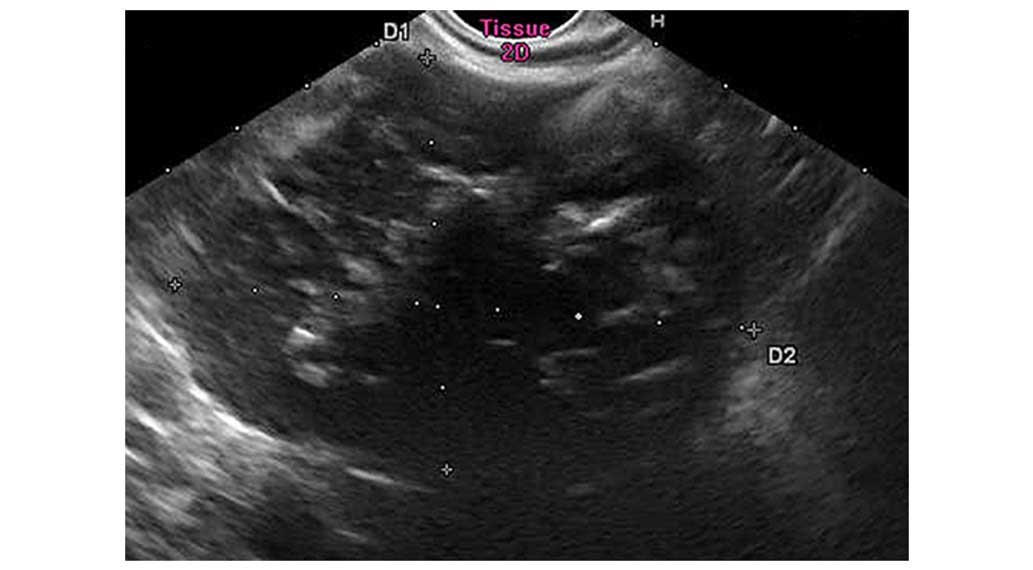

The endosonography revealed a 71×51-mm retroperitoneal mass infiltrating into the pancreas hook, indicating neuroendocrine carcinoma originating from the pancreas. An endosonography-guided fine-needle aspiration biopsy revealed chronic inflammation and lymphadenosis (Fig. 2).

Figure 2.

Endosonography. A retroperitoneal mass was detected infiltrating the pancreas hook.